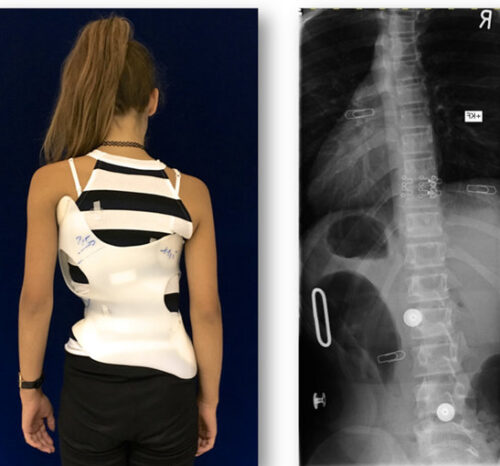

يعتمد علاج اعوجاج العمود الفقري للأطفال والمراهقين على خطط علاجية متعددة، ويُعدّ حزام اعوجاج العمود الفقري (Spinal Brace) أحد أهم الوسائل غير الجراحية. بعد فترة من ارتداء الحزام، يُطلب عادةً من الطفل إجراء الأشعة لمتابعة تقدم العلاج وقياس التحسن في زاوية الانحناء. ولكن يتساءل كثير من الأهل: ما هو الوقت الأمثل لإجراء الأشعة بعد خلع الحزام؟ وهل هناك خطوات يجب اتباعها لضمان نتائج دقيقة؟ في هذا المقال، سنشرح كل التفاصيل ونجيب عن أسئلة الأهل الأكثر شيوعًا.

الحزام يعمل على تقويم العمود الفقري ومنع تفاقم الانحناء أثناء النمو. لكن أثناء ارتدائه، يضغط الحزام على العمود الفقري ويعيد توزيع القوة لتصحيح الانحناء.

عادة لا. الصور ستكون مضللة ولن تعكس زاوية الانحناء الطبيعية. تُستخدم الأشعة أثناء ارتداء الحزام فقط لمتابعة وضع الحزام نفسه أو للتأكد من ثباته.

التطور الكبير في تصميم الأحزمة الطبية جعل علاج اعوجاج العمود الفقري عند المراهقين أكثر نجاحًا وأقل إزعاجًا. باستخدام تقنيات التصوير الثلاثي الأبعاد والمحاكاة الرقمية، أصبح الحزام أكثر خفة وراحة، ويعطي نتائج أفضل في تصحيح الانحناء والتواء العمود الفقري.